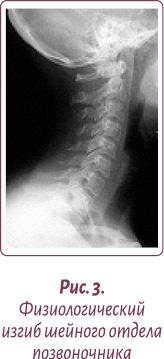

Нормальной статикой шеи считается небольшой физиологический лордоз (прогиб шеи вглубь) (рис. 3).